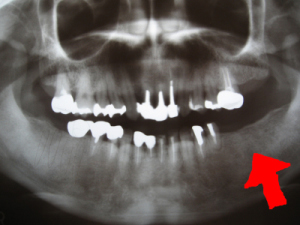

4本のインプラントを入れた状態のレントゲン写真 |

レントゲンで問題がない事を確認してからインプラントした所でご飯が食べれるよう仮の歯(プラスチック)の歯を作ります。 無事終了。 インプラント 1本7万円(税別)2010年年06月現在 |